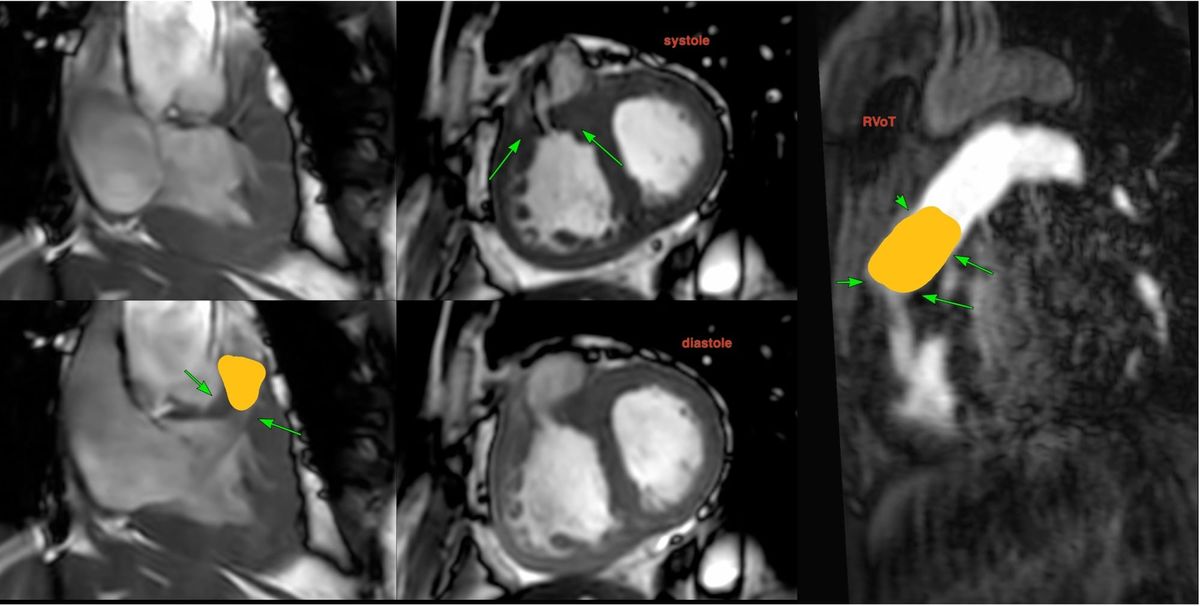

Cardiac MRI shows marked RV hypertrophy, the cause of which is abnormal musculature in the subpulmonic region, dividing the heart into a high-pressure proximal chamber and a low-pressure distal chamber, a double-chambered right ventricle or DCRV.

In this case, there are abnormal septo-parietal and septo-marginal trabeculae causing the stenosis.